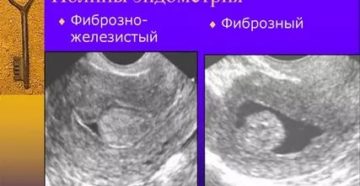

Схема лечения фиброзно-железистого полипа эндометрия Полипами матки называют доброкачественные образования эндометрия во внутренней полости матки….